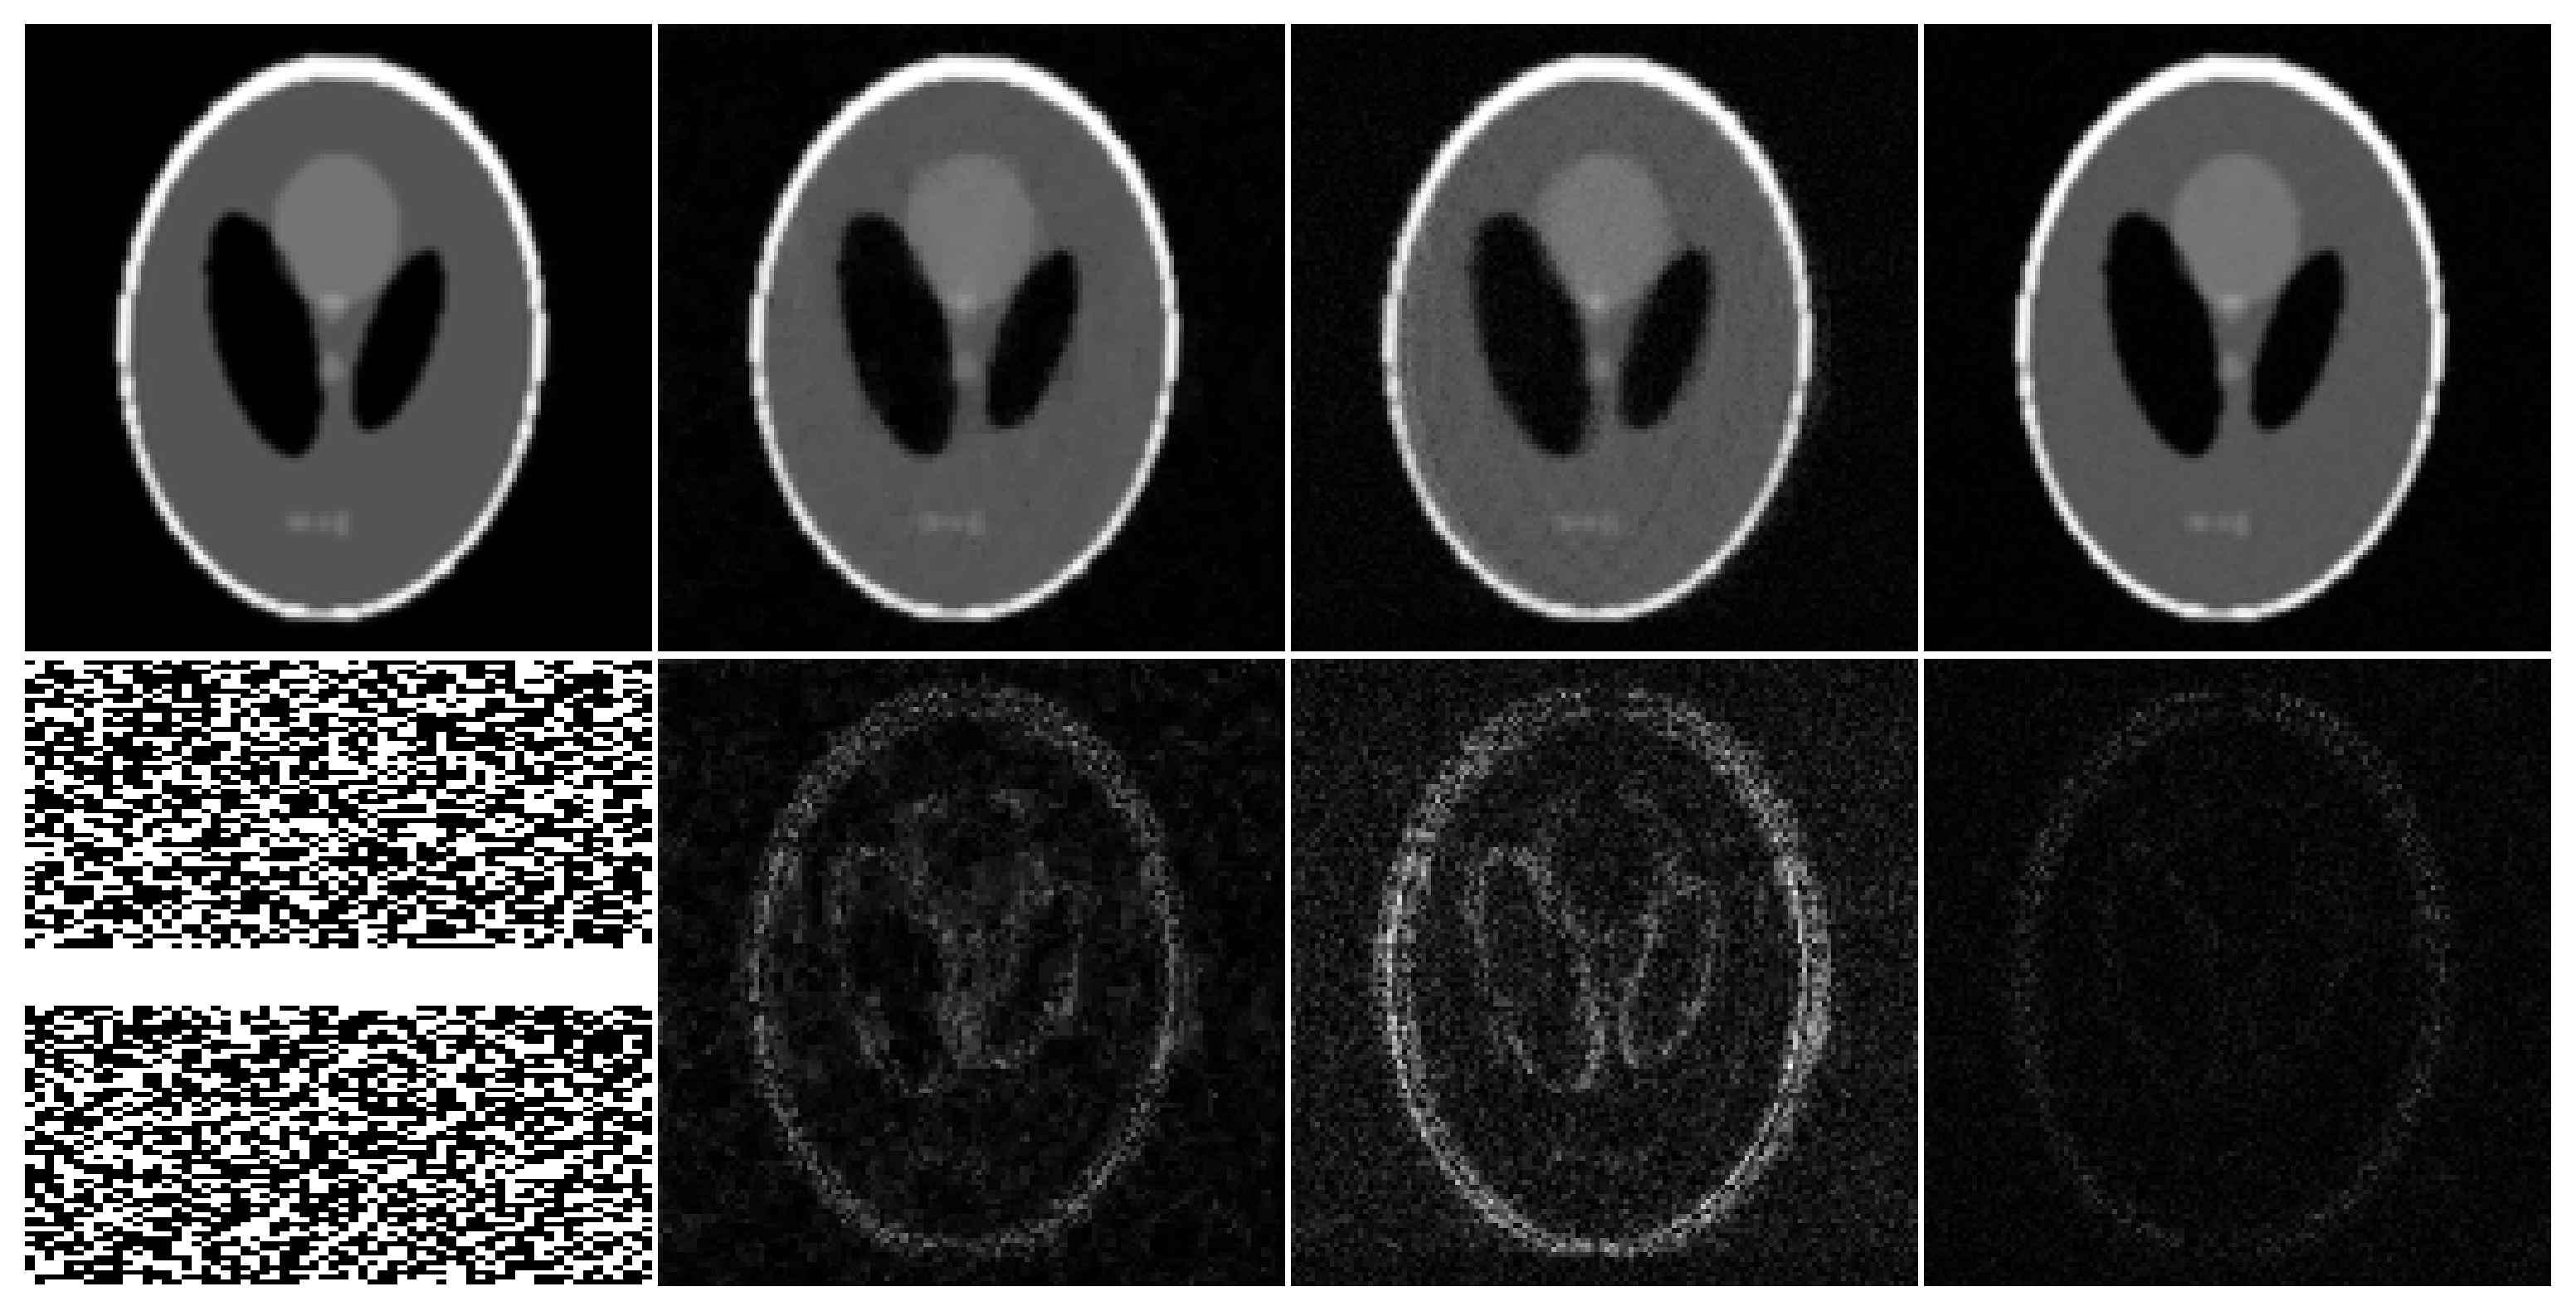

Refer to captionTrueCSL+SDIPDISCUS-GSDISCUS

Fig.ย 3: Top row: A representative frame from a simulated LGE image series with a pronounced myocardial scar. Bottom row: sampling mask (frames: left-right, phase-encoding: top-bottom, frequency-encoding: not shown) and ร—8absent8\times 8 error maps.

We performed reconstructions using CS, L+S, DIP, DISCUS, and DISCUS without group sparsity (DISCUS-GS). These methods were compared in terms of NMSE and SSIM. The results are summarized in Tableย 2. DISCUS outperforms CS, L+S, and DIP by a wide margin for both NMSE and SSIM. These results also show that removing group sparsity worsens the performance by approximately one dB. Fig.ย 3 shows a representative frame from one of the image series. Compared to DISCUS, CS exhibits excessive blurring around the myocardial scar, DIP exhibits excessive noise, and L+S exhibits a more structured error map.